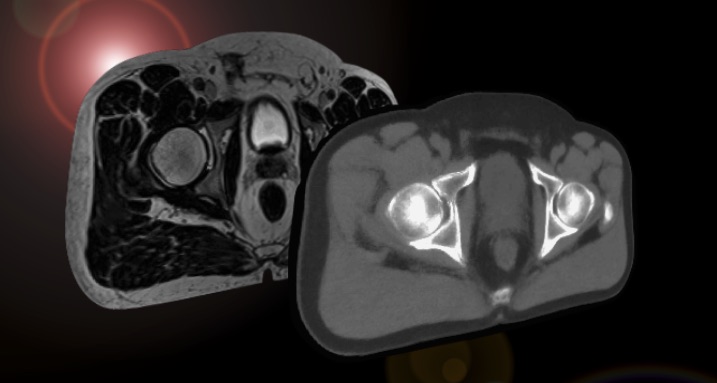

• MRI Planner

Image

A CNN based software trained to analyze MR images and identify organ structures and tissue densities that are of importance in radiotherapy planning.